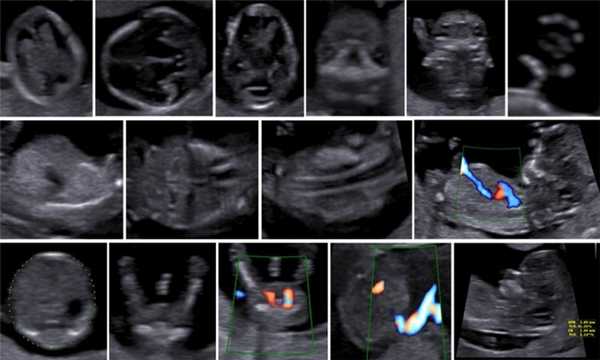

Копчико-теменной размер плода (КТР) для проведения скрининга I триместра должен быть в пределах 45-84 мм. Для оценки носовой кости в I триместре беременности необходимо соблюдать строгие условия. Это адекватное увеличение (на снимке должны быть только голова и верхняя часть грудной клетки), среднесагиттальный скан (должны быть визуализированы эхогенный кончик носа, небный отросток верхней челюсти, диэнцефалон), нос представлен тремя "К" (кончик носа, кожа, кость). Кожные покровы и кости носа визуализируются в виде знака "равенства", нос параллелен датчику.

Такие правила, как размер плода, адекватное увеличение, среднесагиттальный скан идентичны таковым при измерении ТВП. Таким образом, при выведении корректного скана для измерения ТВП, что является обязательным при проведении УЗ-исследования в сроки 11-14 нед беременности, оценка носовой кости проводится в том же самом срезе, не требуя получения дополнительных изображений.

Если все критерии соблюдены, то на уровне носа плода должны быть видны три четко различимые линии: верхняя линия представляет собой кожу, книзу от нее визуализируется более толстая и более эхогенная, чем кожа носовая кость. Третья линия, визуализируемая кпереди от носовой кости и на более высоком уровне, чем кожа - это кончик носа (рис. 1).

Рис. 1. Нормальная носовая кость.

Считается, что носовая кость нормальна, когда она по своей структуре более эхогенна, чем надлежащая кожа и патологична, если она не видна (аплазия) (рис. 2) или ее длина меньше нормы (гипоплазия) (рис. 3). В случае одинаковой или меньшей эхогенности носовой кости чем кожи носовая кость считается патологической (рис. 4).